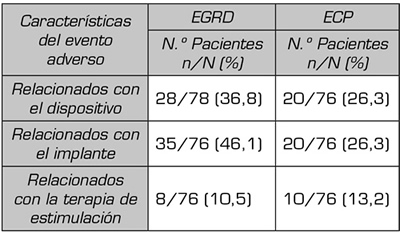

Las complicaciones más frecuentes que aparecieron en el estudio Accurate (12) son clasificadas según las características del evento adverso, observando que predominan las complicaciones relacionadas con el procedimiento del implante, superando las aparecidas en el grupo de ECP. Plantean que la menor experiencia y cierta mayor dificultad de la técnica pueden se la causa de este resultado (Tabla II).

Tabla II. Distribución de los efectos adversos según sus características en el estudio Accurate